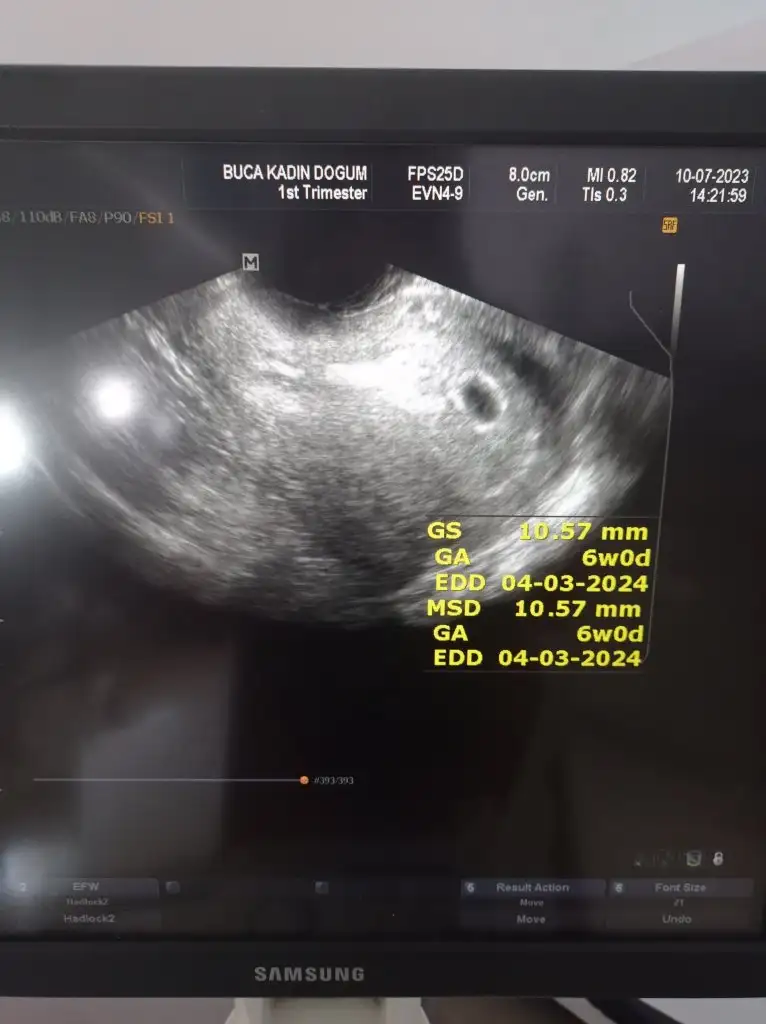

Kızlar bende size katılabilir miyim .2024 annesi olucam nasipse. Benimde ultrason u yorumlarmisiniz 6+0 vajinal muayene .birde kesenin içinde iki tane yuvarlak yok mu

Eklentiler

• IMG_20230710_140421.webp

IMG_20230710_140421.webp

28,3 KB · Görüntüleme: 56